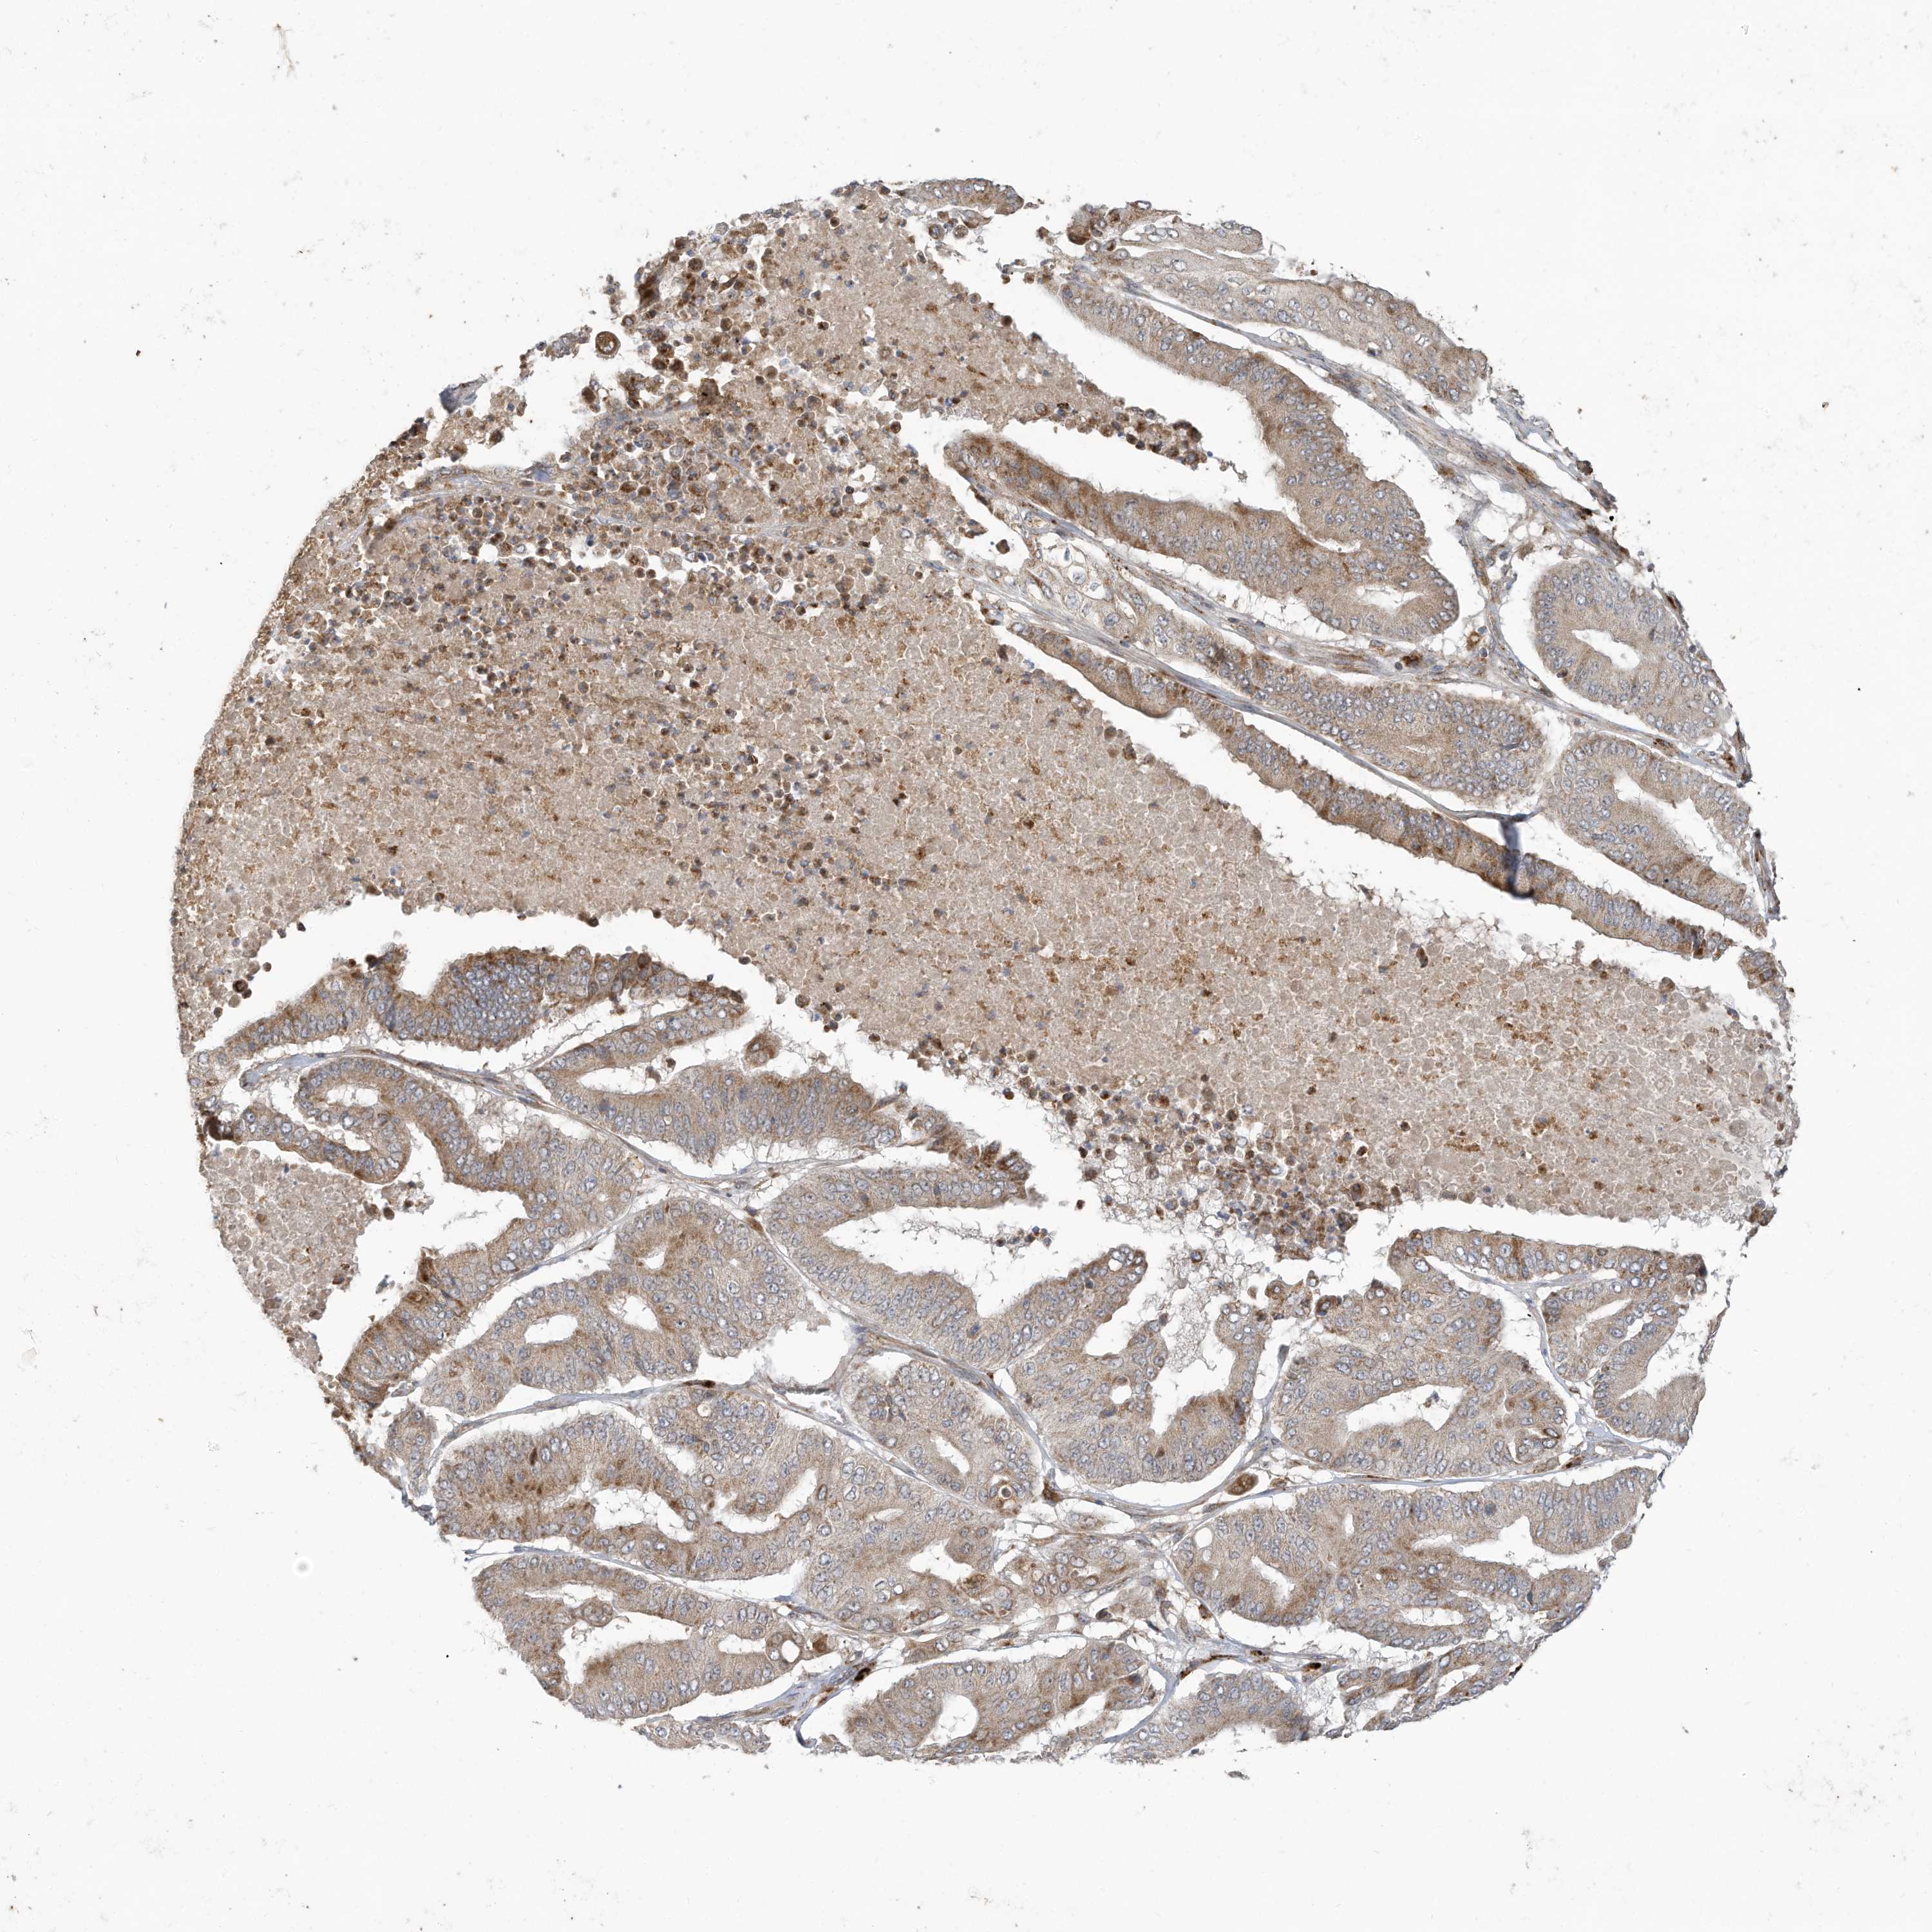

PANCREATIC CANCER - Protein expressioni

A mouse-over function shows sample information and annotation data. Click on an image to view it in a full screen mode. Samples can be filtered based on level of antibody staining by selecting one or several of the following categories: high, medium, low and not detected. The assay and annotation is described here.

Note that samples used for immunohistochemistry by the Human Protein Atlas do not correspond to samples in the TCGA dataset.

Antibody stainingi

Antibody staining in the annotated cell types in the current human tissue is reported as not detected, low, medium, or high, based on conventional immunohistochemistry profiling in selected tissues. This score is based on the combination of the staining intensity and fraction of stained cells.

Each image is clickable and will lead to virtual microscopy that enables deeper exploration of all samples and also displays staining intensity scores, fraction scores and subcellular localization as well as patient and tissue information for each sample.

Antibody HPA026826

Staining

High

Medium

Low

Not detected

Intensity

Strong

Moderate

Weak

Negative

Quantity

>75%

75%-25%

<25%

None

Location

Nuclear

Cytoplasmic/membranous

Cytoplasmic/membranous,nuclear

Adenocarcinoma, NOS